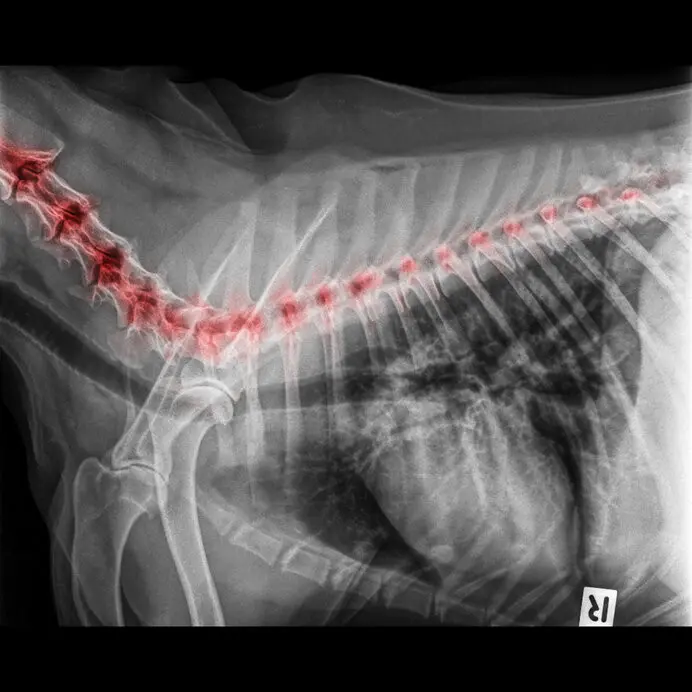

De meest voorkomende plaats voor artrose bij honden is aan de ellebogen, schouders, knieën, heupen en tenen. De aandoening is echter regelmatig over het hele lichaam verspreid, waardoor er dus meerdere gewrichten worden aangetast.

Artrose aan de nek of rugwervels is dus ook heel goed mogelijk. De aandoening is, in tegenstelling tot slijtage van de gewrichten, géén ouderdomskwaal.

Om artrose vast te stellen, zal uw dierenarts een lichamelijk onderzoek doen, vaak gecombineerd met röntgenfoto's om te zien in hoeverre het kraakbeen is aangetast. Röntgenbeelden geven een goed beeld van de slijtage en de veranderingen in het gewricht.